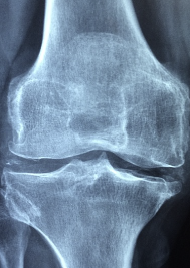

퇴행성 관절염 완치하는 최고의 비법을 한번 알아보도록 하겠습니다. 퇴행성 관절염은 관절의 연골이 손상되어 관절에 통증, 염증, 변형 등의 증상을 일으키는 질환입니다. 퇴행성 관절염은 나이가 들면서 자연스럽게 발생할 수 있는 질환입니다.

퇴행성 관절염의 원인은 다양하지만, 대체로 연령, 비만, 유전적 요인, 외상, 스포츠 등의 요인으로 인해 발생합니다. 연령이 높을수록 관절의 노화와 함께 연골의 두께가 얇아지고 탄력이 감소하여 연골 파손이 발생할 가능성이 높아지는데, 이는 주로 손, 무릎, 엉덩이, 척추 등 대형 관절에서 발생합니다. 비만은 체중이 증가함에 따라 관절 부하가 증가하여 연골 파손을 유발할 수 있으며, 유전적 요인도 관절의 노화와 연골의 성장 및 탄력에 영향을 미칩니다. 외상이나 스포츠는 관절을 직접적으로 손상시켜 연골 파손을 초래할 수 있습니다. 또한, 관절과 관련된 질환, 예를 들어 류마티스 관절염, 골관절염, 척추 관절염 등도 퇴행성 관절염의 원인이 될 수 있습니다.